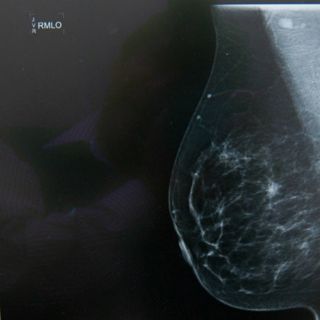

'Thermy' usará inteligencia artificial para registrar el calor de la piel con una cámara termográfica

Si bien, Thermy será una alternativa de detección oportuna porque analizará imágenes termográficas y datos clínicos mediante las técnicas de visión e inteligencia artificial, el ingeniero aclaró que no suple a la mastografía ni la vigilancia médica.